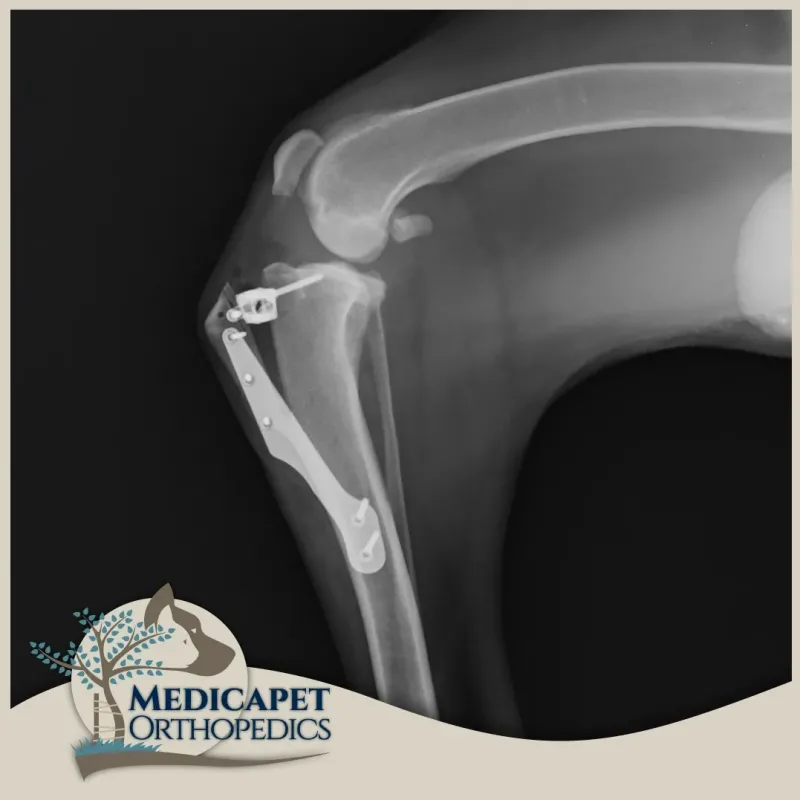

Bu ameliyatlar, diz ekleminin biyomekaniğini ve geometrisini, stabiliteyi korumak için ön çapraz bağa gerek kalmayacak şekilde değiştirir. Teknikte, kemiği keserek ve yeni bir pozisyonda sabitleyerek kaval kemiğinin üst kısmının yeniden şekillendirilmesini içeren birkaç varyasyon vardır. Medicapet olarak bu tekniklerin tümünü gerçekleştiriyor olabilmekle birlikte, yapılan bilimsel çalışmalar ışığında uzun vadede en sağlıklı teknikler olarak sunulan TTA ve TPLO cerrahilerini uygulamayı tercih ediyoruz.

Bu ameliyat, tibianın üst kısmında dairesel bir kesi oluşturulmasını ve kemikteki önceki eğim artık mevcut olmayana kadar plato segmentinin döndürülmesini içerir. Daha sonra kemik, kemik plakası ve vidalar kullanılarak bu yeni pozisyonda sabitlenir. Böylece femurun tibia üzerinde uygunsuz şekilde kayması engellenmiş olur. Hassas ölçümler ve kusursuz el maniplasyonu gerektirdiği için tecrübeli ve ehil cerrahlar tarafından uygulanmalıdır.

Kemik iyileşmesinin bağ iyileşmesinden daha kolay ve hızlı olması sebebiyle, bu onarımlar hasarlı bağın değiştirilmesi için tasarlanan ameliyatlardan önemli ölçüde daha sağlamdır. En büyük pratik fayda, tüm köpeklerin 1-3 gün içinde ameliyat edilen uzuvda ağırlık taşımaya başlamasının beklenmesiyle, uzuv kullanımının çok güvenilir bir şekilde geri dönmesidir. TPLO ve TTA'nın mekanik avantajları, hızlı işleve dönüşle birleştiğinde, özellikle ağır köpekler, atletik hayvanlar, hafif aksama

gösteren hayvanlar ve her iki diz eklemini de etkileyen ön çapraz bağ yaralanmaları olan hayvanlar için önemlidir. Her iki dizini aynı anda etkileyen ön çapraz bağ yaralanmaları olan bazı hayvanlarda, TPLO tek bir ameliyatta her iki diz eklemine uygulanabilir. Bağ değiştirme teknikleri kullanıldığında bu mümkün değildir.

Köpeklerin %90'ından fazlası TPLO veya TTA'dan sonra normal aktivitelerine döner. Hatta her iki tekniği kedilere de başarıyla uygulayabiliyoruz. Bu operasyonlardan sonra kedi ve köpeklerin devam eden ilaç tedavilerine gerek kalmadan sınırlandırılmamış egzersize dönmelerini bekliyoruz. TPLO ve TTA için başarı oranları birbirine çok benzerdir.

Deneyimli cerrahlar çapraz bağ onarım ameliyatı yaptığında komplikasyon oranları düşüktür. En yaygın iki komplikasyon enfeksiyon ve mekanik komplikasyonlardır. Enfeksiyon antibiyotiklerle tedavi edilir. Hayvanların büyük çoğunluğunda, implantlar ömür boyu yerinde kalır ve hiçbir soruna neden olmaz. Mekanik komplikasyonlar genellikle kemikler iyileşmeden önce çok fazla egzersiz yapan köpeklerde görülür. Birçok mekanik komplikasyon sadece istirahatle giderilebilir ancak bazı sorunlar cerrahi revizyon gerektirir.